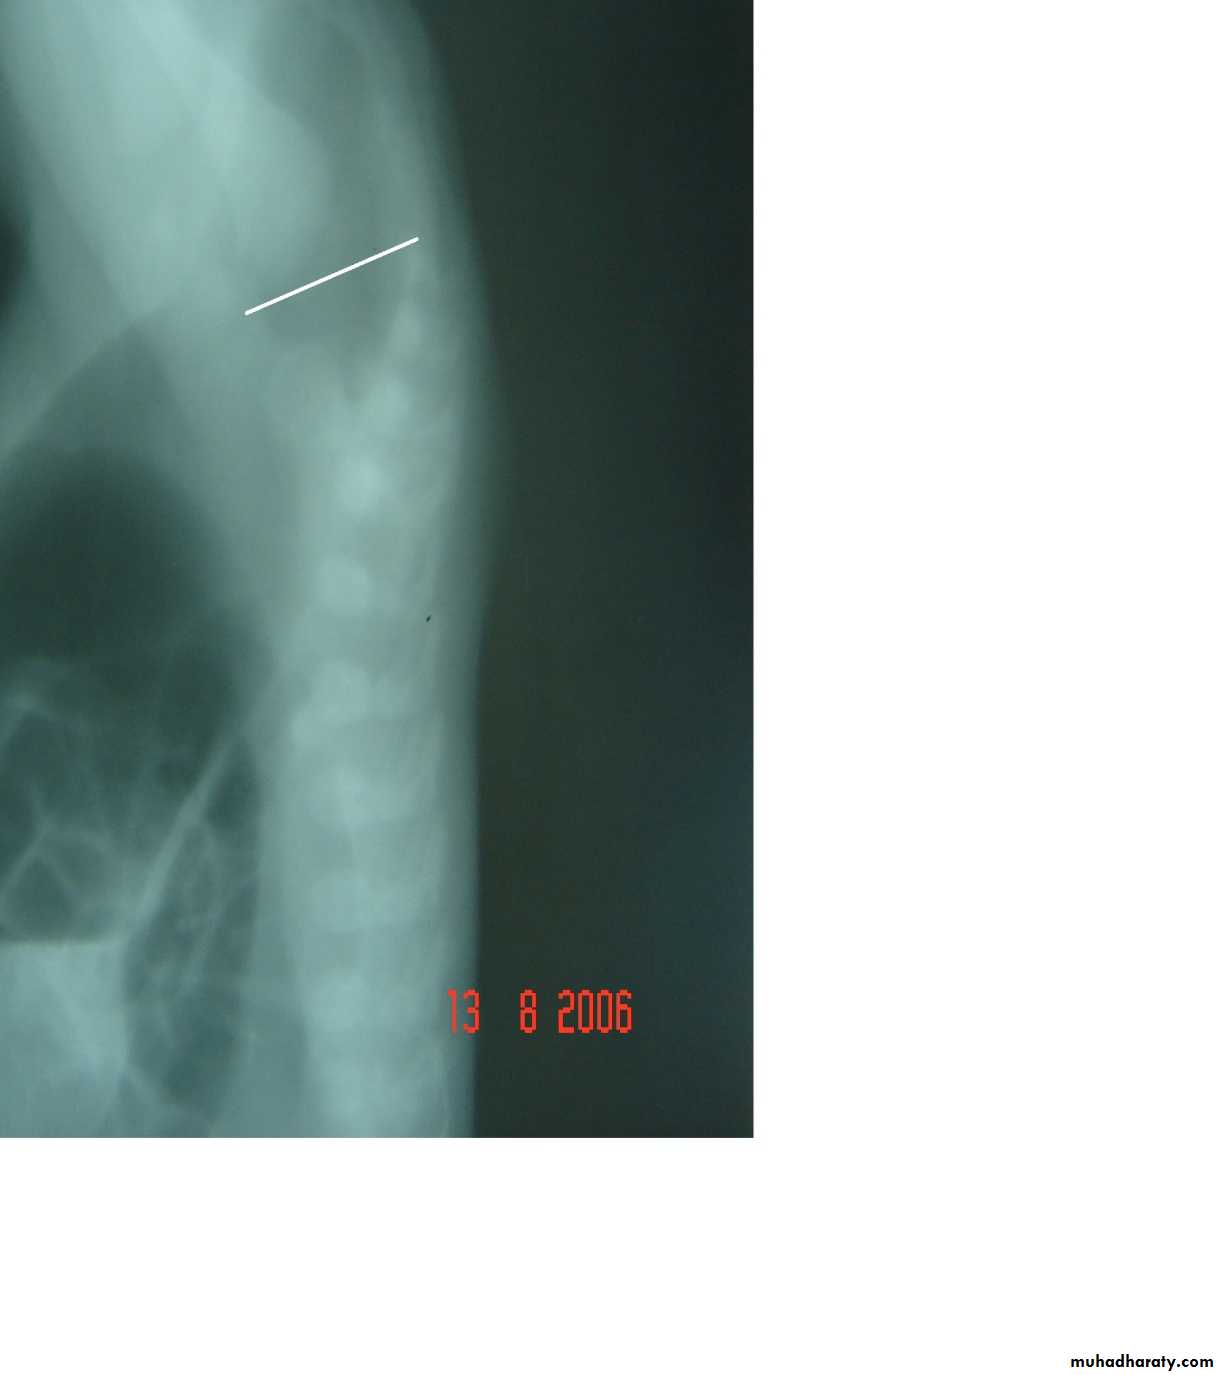

Hirschprungs disease